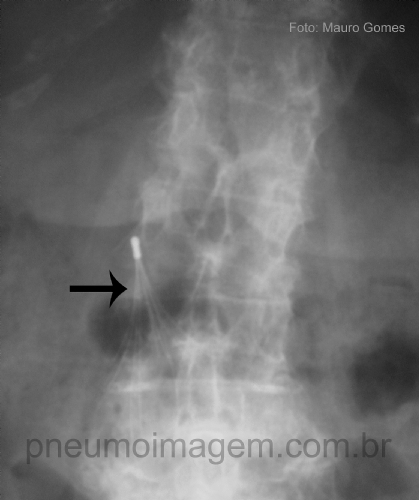

O caso desse mês é uma imagem curiosa. O que a seta aponta? Deixe seus comentários abaixo.

The case of this month is a curious image. What the arrow points? Write your comment below.